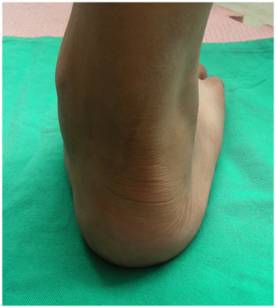

| 多趾征 – 从正后方观察患足,如果外侧缘看到超过两个以上的足趾,则提示多趾征阳性

|